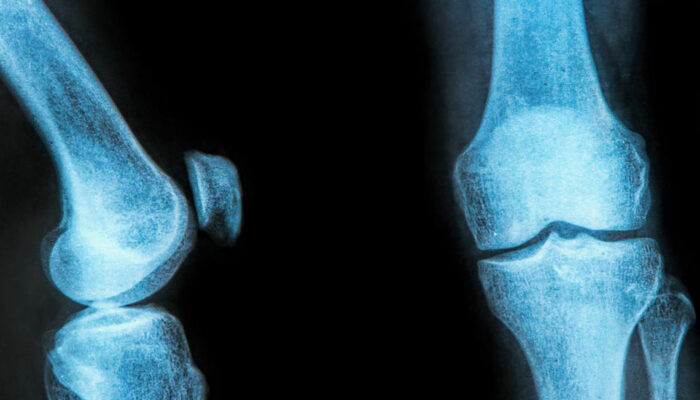

The rubbery C-shaped disc cushioning your knee is a meniscus. There are two menisci in each knee. One at the inner side and the other on the outer side. It is this meniscus that helps to keep your knee steady. It balances your body weight around your knee. If there is a tear in the meniscus, you will experience a lot of pain.